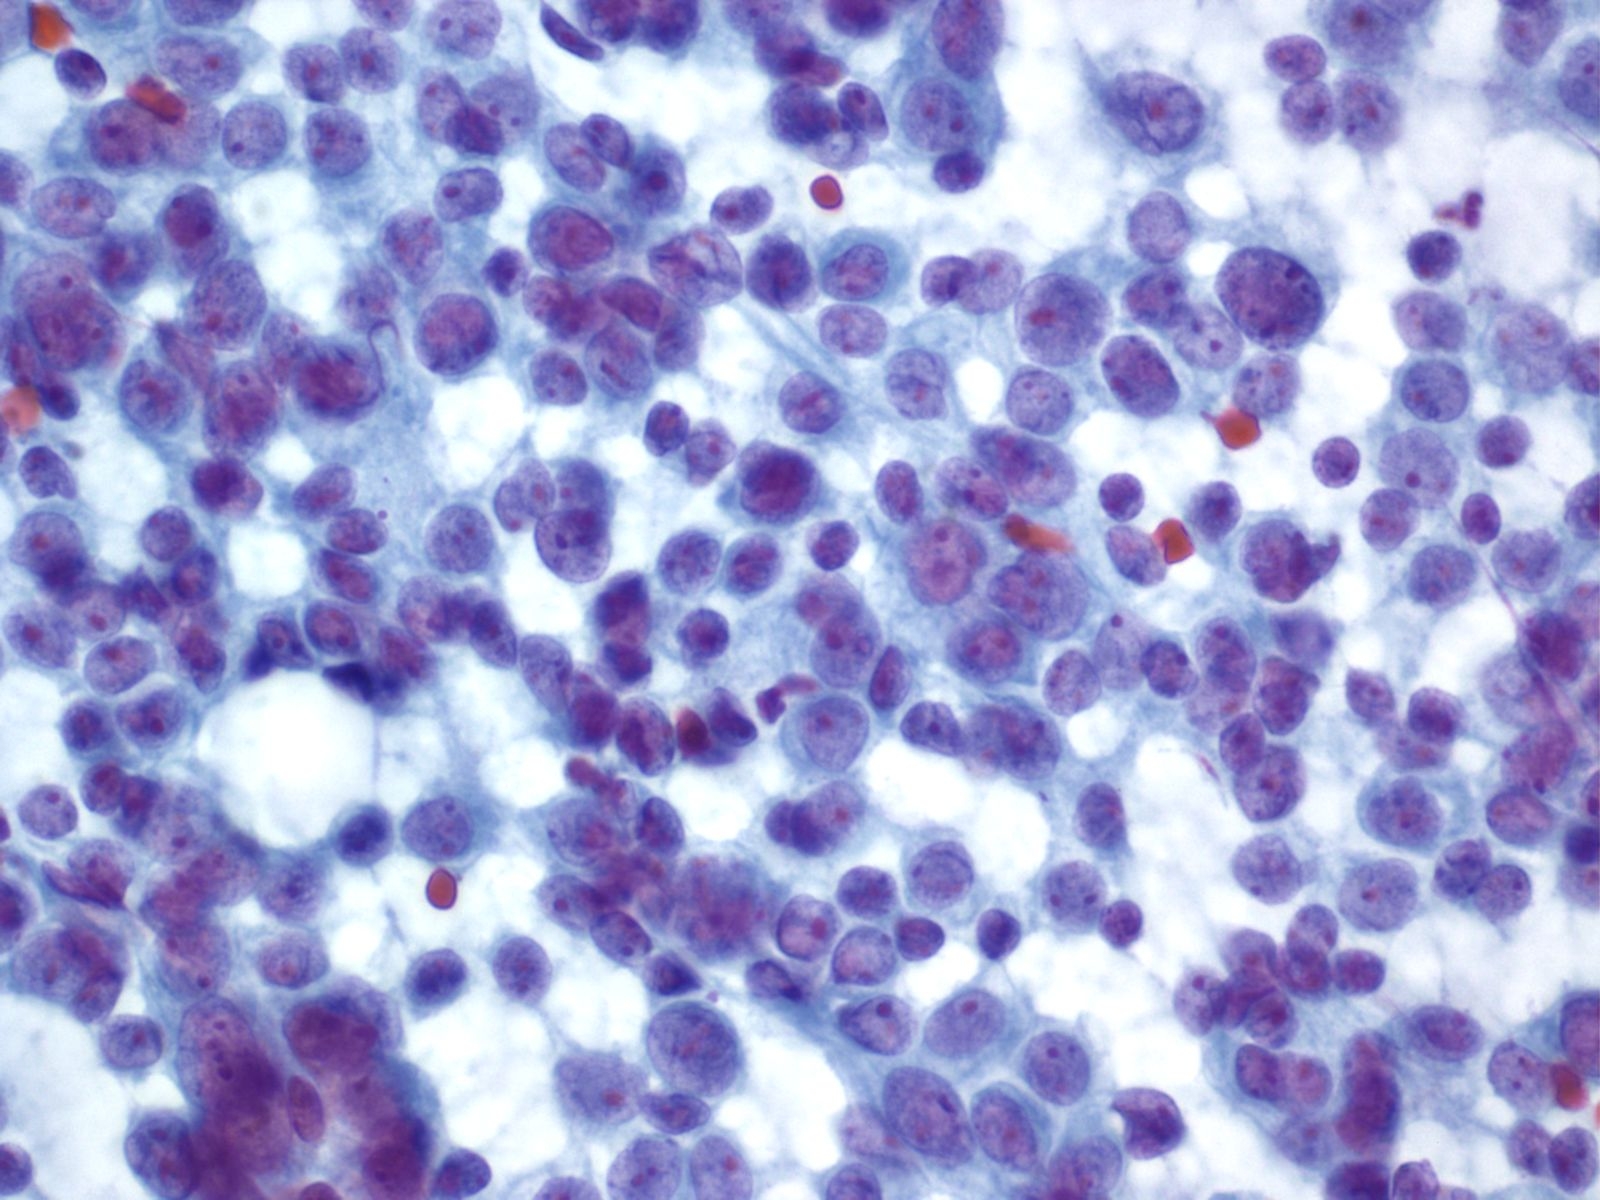

Acinar Cell Carcinoma – PAN2-036

- Incidence: ~1-2% of adult pancreatic neoplasms

- Age,Gender: children<<adults; peak incidence, 7th decade; M:F:: 4:1

- Prognosis and Therapy: directly related to tumor stage and is better than for ductal adenocarcinoma. Resection is treatment of choice.

- Radiological Features: Solid masses with well demarcated borders; rarely cystic

Key Cytological Features: Acinar Cell Carcinoma

- Solid-cellular smear pattern of monomorphic cells

- Cellular clusters of various sizes and single cells (loss of organoid "grape-like Clustering of benign acinar tissue)

- Stripped naked nuclei; +/- loose cytoplasmic granules (best noted on Hand E stain)

- May be disarmingly bland, with a polygonal cell shape and low N:C

- Coarse chromatin usually with prominent nucleoli, but not always granular cytoplasm, variably prominent